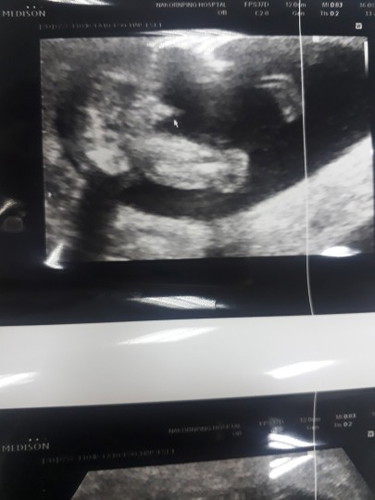

หญิงหรือชายค่ะ

หมอบอกว่าผู้ชาย99%จริงไหมค่ะ

ตอน4เดือน ของเราเห็นจู๋แบบนี้เลยค่ะ หมอฟันธงผู้ชาย พอมาวันนี้5เดือน จู๋หายไปเฉยเลย หมอบอกสงสัยเค้าจะหลอกหมอแล้ว กลายเป็น ผญ.เฉยเลย อิแม่งงมาก

กะจู๋โผล่ออกมาชาย100%ค่ะ บ้านนี่หมอฟันธงตั้งแต่4เดือนเลยค่ะ

น่าจะชายนะคะเหมือนของบ้านนี้เลย หมอบอก 90%คะ

ชายค่ะ น้องจู๋ออกมาแบบนี้

ชายค่ะ. จู่โผล่ชัดเลย